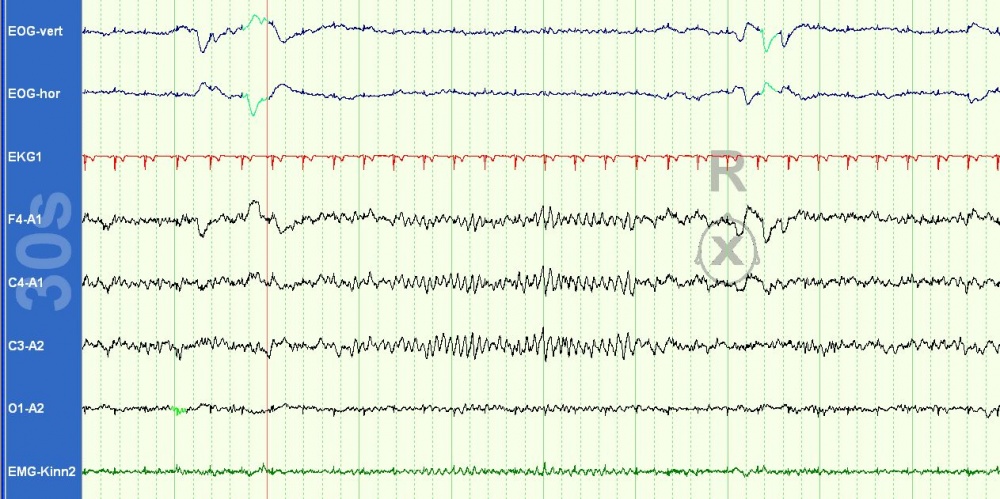

Elektrookulogramm („EOG“, Spuren 1 und 2) sind ruckartig schnelle Augenbewegungen zu beobachten, das

Elektroencephalogramm („EEG“, Spuren 4 bis 7) zeigt wechselweise einen alpha- oder theta-Rhythmus, die

Elektromyografie („EMG“, Spur 8) weist einen sehr niedrigen Muskeltonus auf.

Das vorbeschriebene Schlaf-Apnoe-Syndrom konnte mittels Polysomnografie (Abbildung 1) ausgeschlossen werden, die Kernspintomografie des Neurocraniums zeigte einen unauffälligen Befund, Hinweise auf eine Stoffwechselstörung oder tiefgreifende psychiatrische Begleiterkrankung fanden sich nicht.

Die Polysomnografie spielt bei Diagnostik/Ausschluss organischer schlafgebundener Erkrankungen eine Schlüsselrolle. Sie gibt einen detaillierten Einblick in die körperlichen Vorgänge während des Schlafes [11, 22]. Mit Hilfe verschiedener Messmethoden werden u. a. die unterschiedlichen Schlafstadien, Herzaktivität, Augenbewegungen und Bewegungen der Kaumuskeln bestimmt (Abbildung 2). Gutartiges Schnarchen kann gegenüber krankhaften Atmungsaussetzern abgegrenzt werden, die oftmals mit ausgeprägten Sauerstoffentsättigungen vergesellschaftet sind und ebenfalls zu relevanter Tagesschläfrigkeit führen können [12, 22].